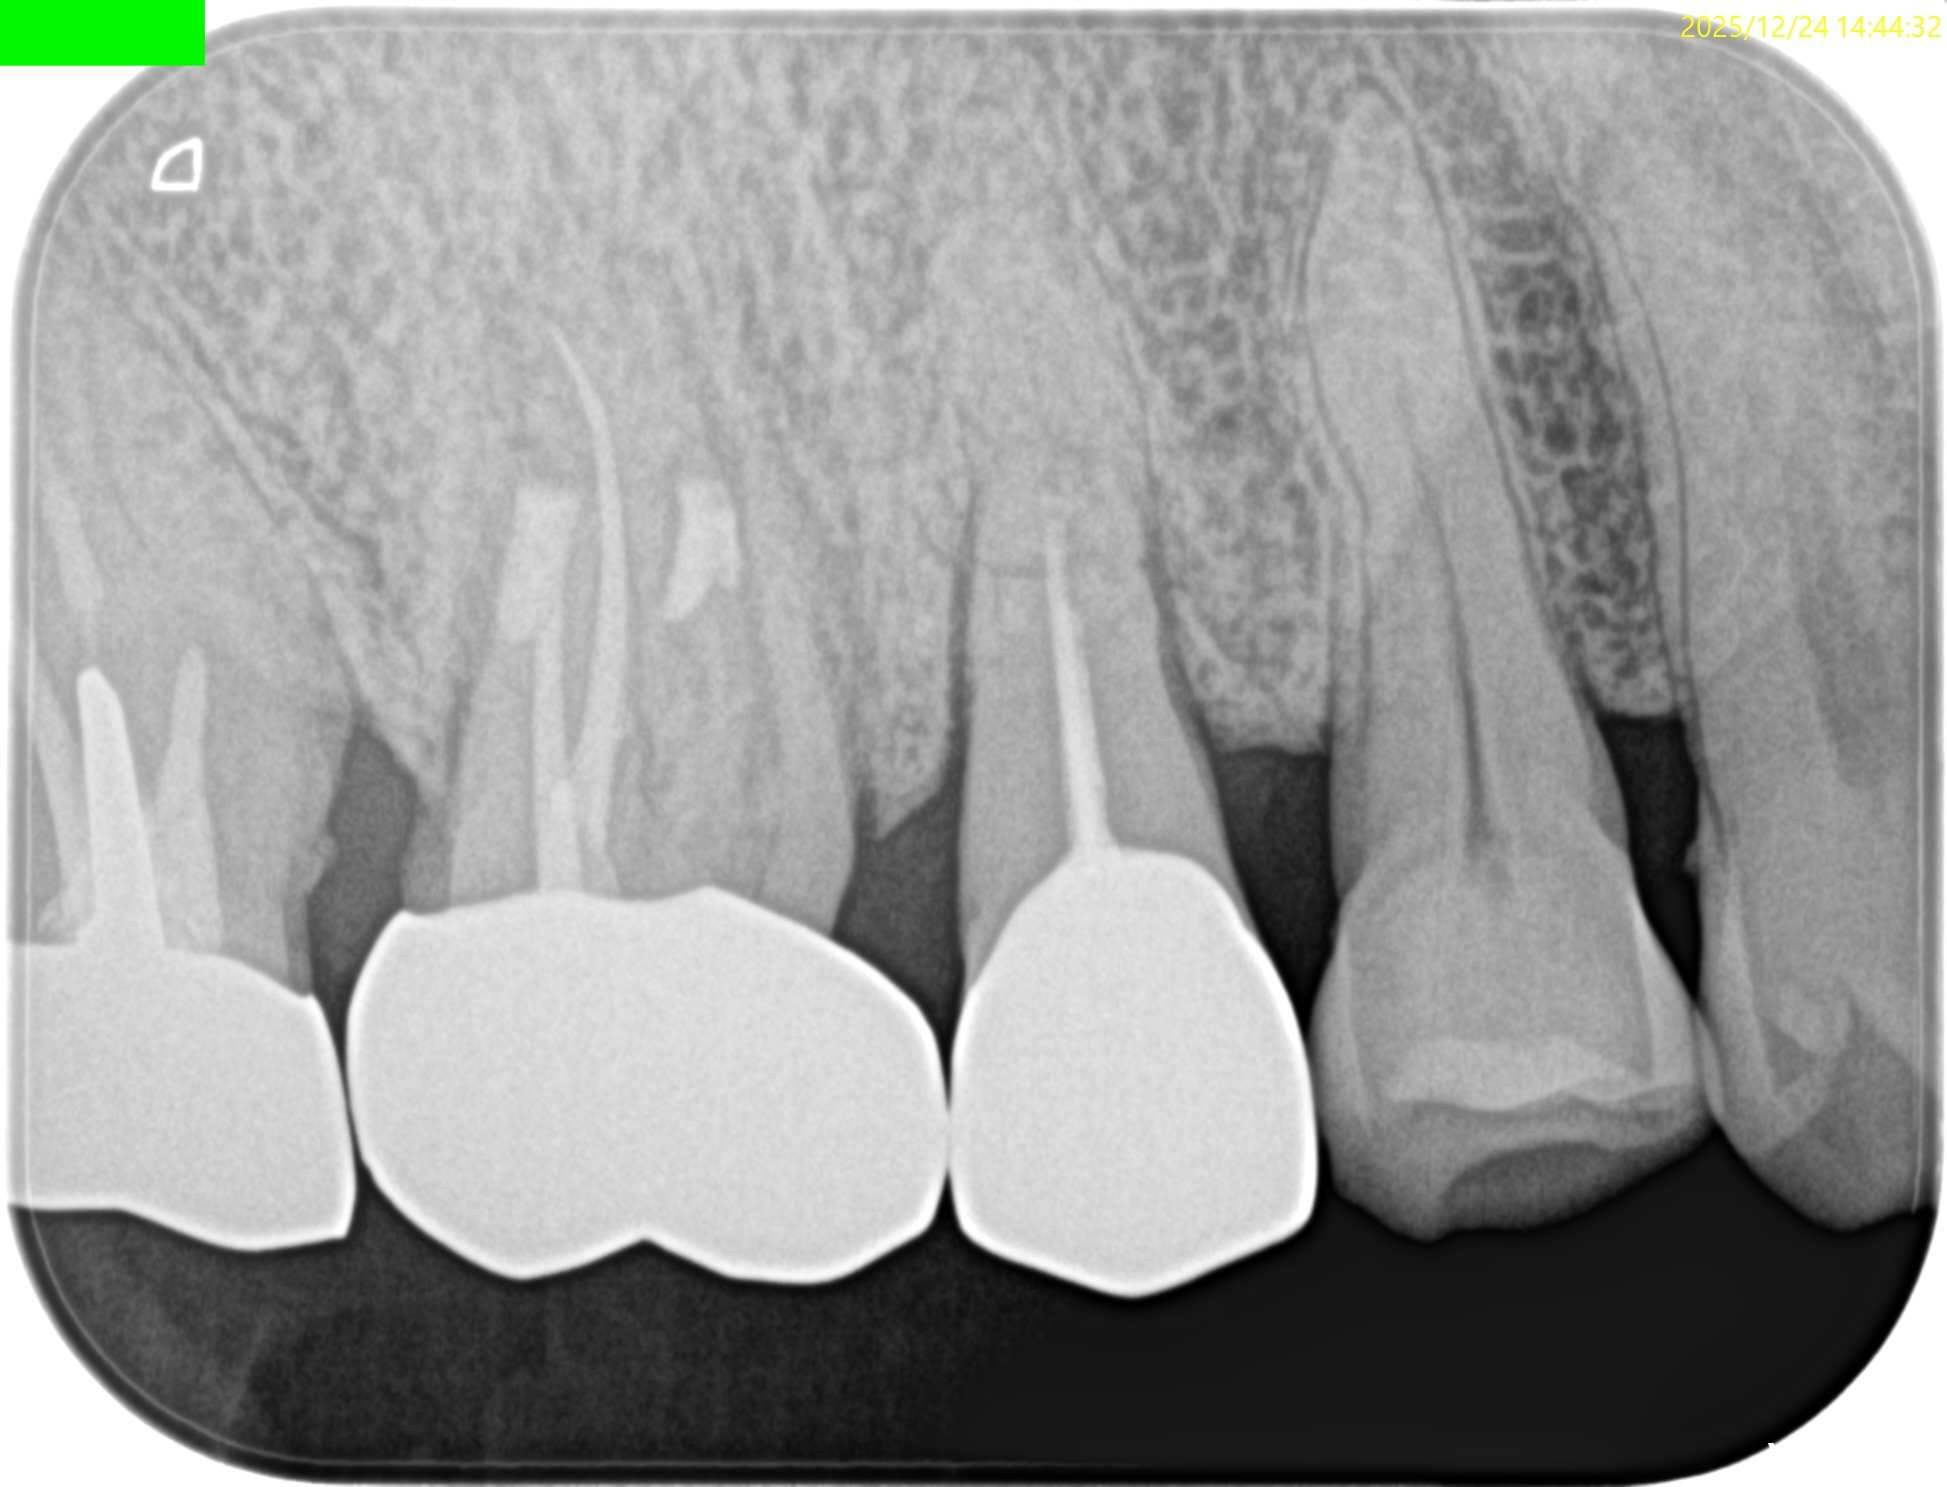

Pre-op PA(2024.11.25)

MBは形成されていない。

ということは通常は根管治療だがSinus tractの存在が治療をApicoectomyへ流れさせている。